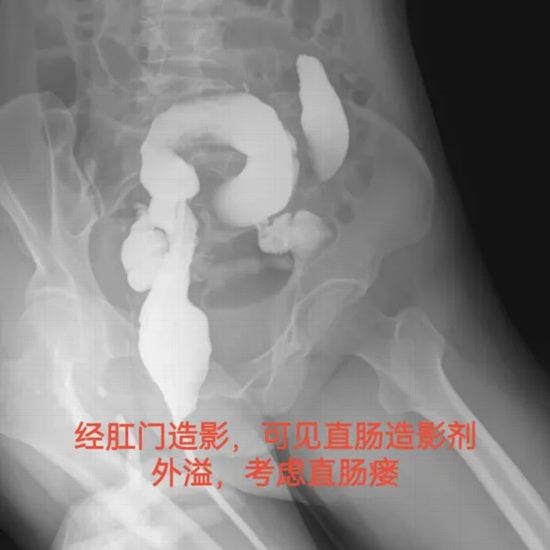

病情简述:52岁女性,宫颈癌术后放疗,盆腔组织严重纤维化。后因肿瘤复发侵犯直肠,形成直肠瘘。

诊疗破局:盆腔放疗导致的组织纤维化是本例治疗的主要难点。盆腔组织血供差,质地脆弱,解剖层次不清,手术风险极高。多学科团队制定了精细的腹腔镜方案,术中以毫米级的谨慎操作完整切除病灶,最大程度保护周围脏器。

技术体现:在“刀锋”上行走,依靠的是对解剖的深刻理解和对生命的极度敬畏。